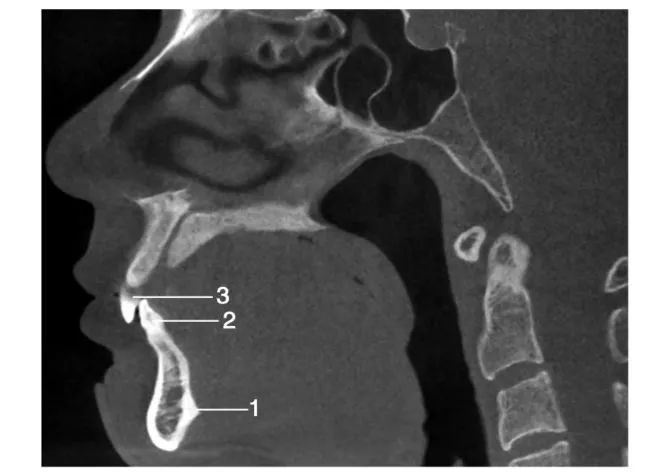

经下颌中线处层面矢状位图像

1.颏棘; 2.下颌中切牙 ; 3.上颌中切牙